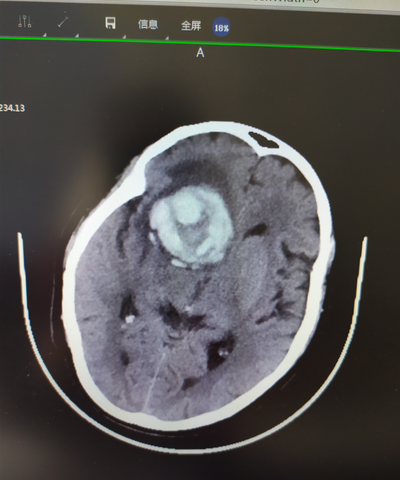

患者女性,66歲,因突然摔傷伴右側(cè)肢體活動不靈6小時余就診。診斷:左側(cè)額葉自發(fā)性腦出血。查體:神志清楚,GCS評分14分,左側(cè)肢體肌力3級,病理征陽性。患者既往有高血壓病史多年,規(guī)律服藥,血壓控制可。該患者出現(xiàn)部位不是典型的高血壓腦出血位置,且血腫呈混雜密度,屬于不穩(wěn)定的腦出血。該患者幕上出血,出血量>20ML,右側(cè)側(cè)腦室額角受壓消失,有手術(shù)指征。

術(shù)前CT顯示